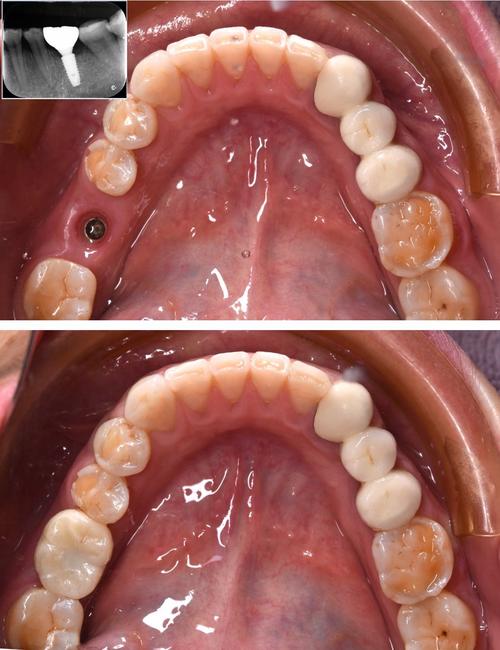

- 即刻种植:拔牙后立即在新鲜拔牙窝内植入种植体,属于“早种”的极端情况,适用于拔牙窝条件理想(无感染、骨量充足、牙龈形态良好)的患者。

- 早期种植:拔牙后4-12周内进行种植,此时拔牙窝内血凝机化完成,炎症风险降低,但牙槽骨尚未发生明显吸收,骨改建初期。

- 延期种植:拔牙后3-6个月及以上,此时牙槽骨已基本完成吸收改建,达到相对稳定状态,是传统种植的常用时间窗。

“早种”一般指即刻或早期种植(拔牙后3个月内),“晚种”则多指延期种植(拔牙后3个月以上)。